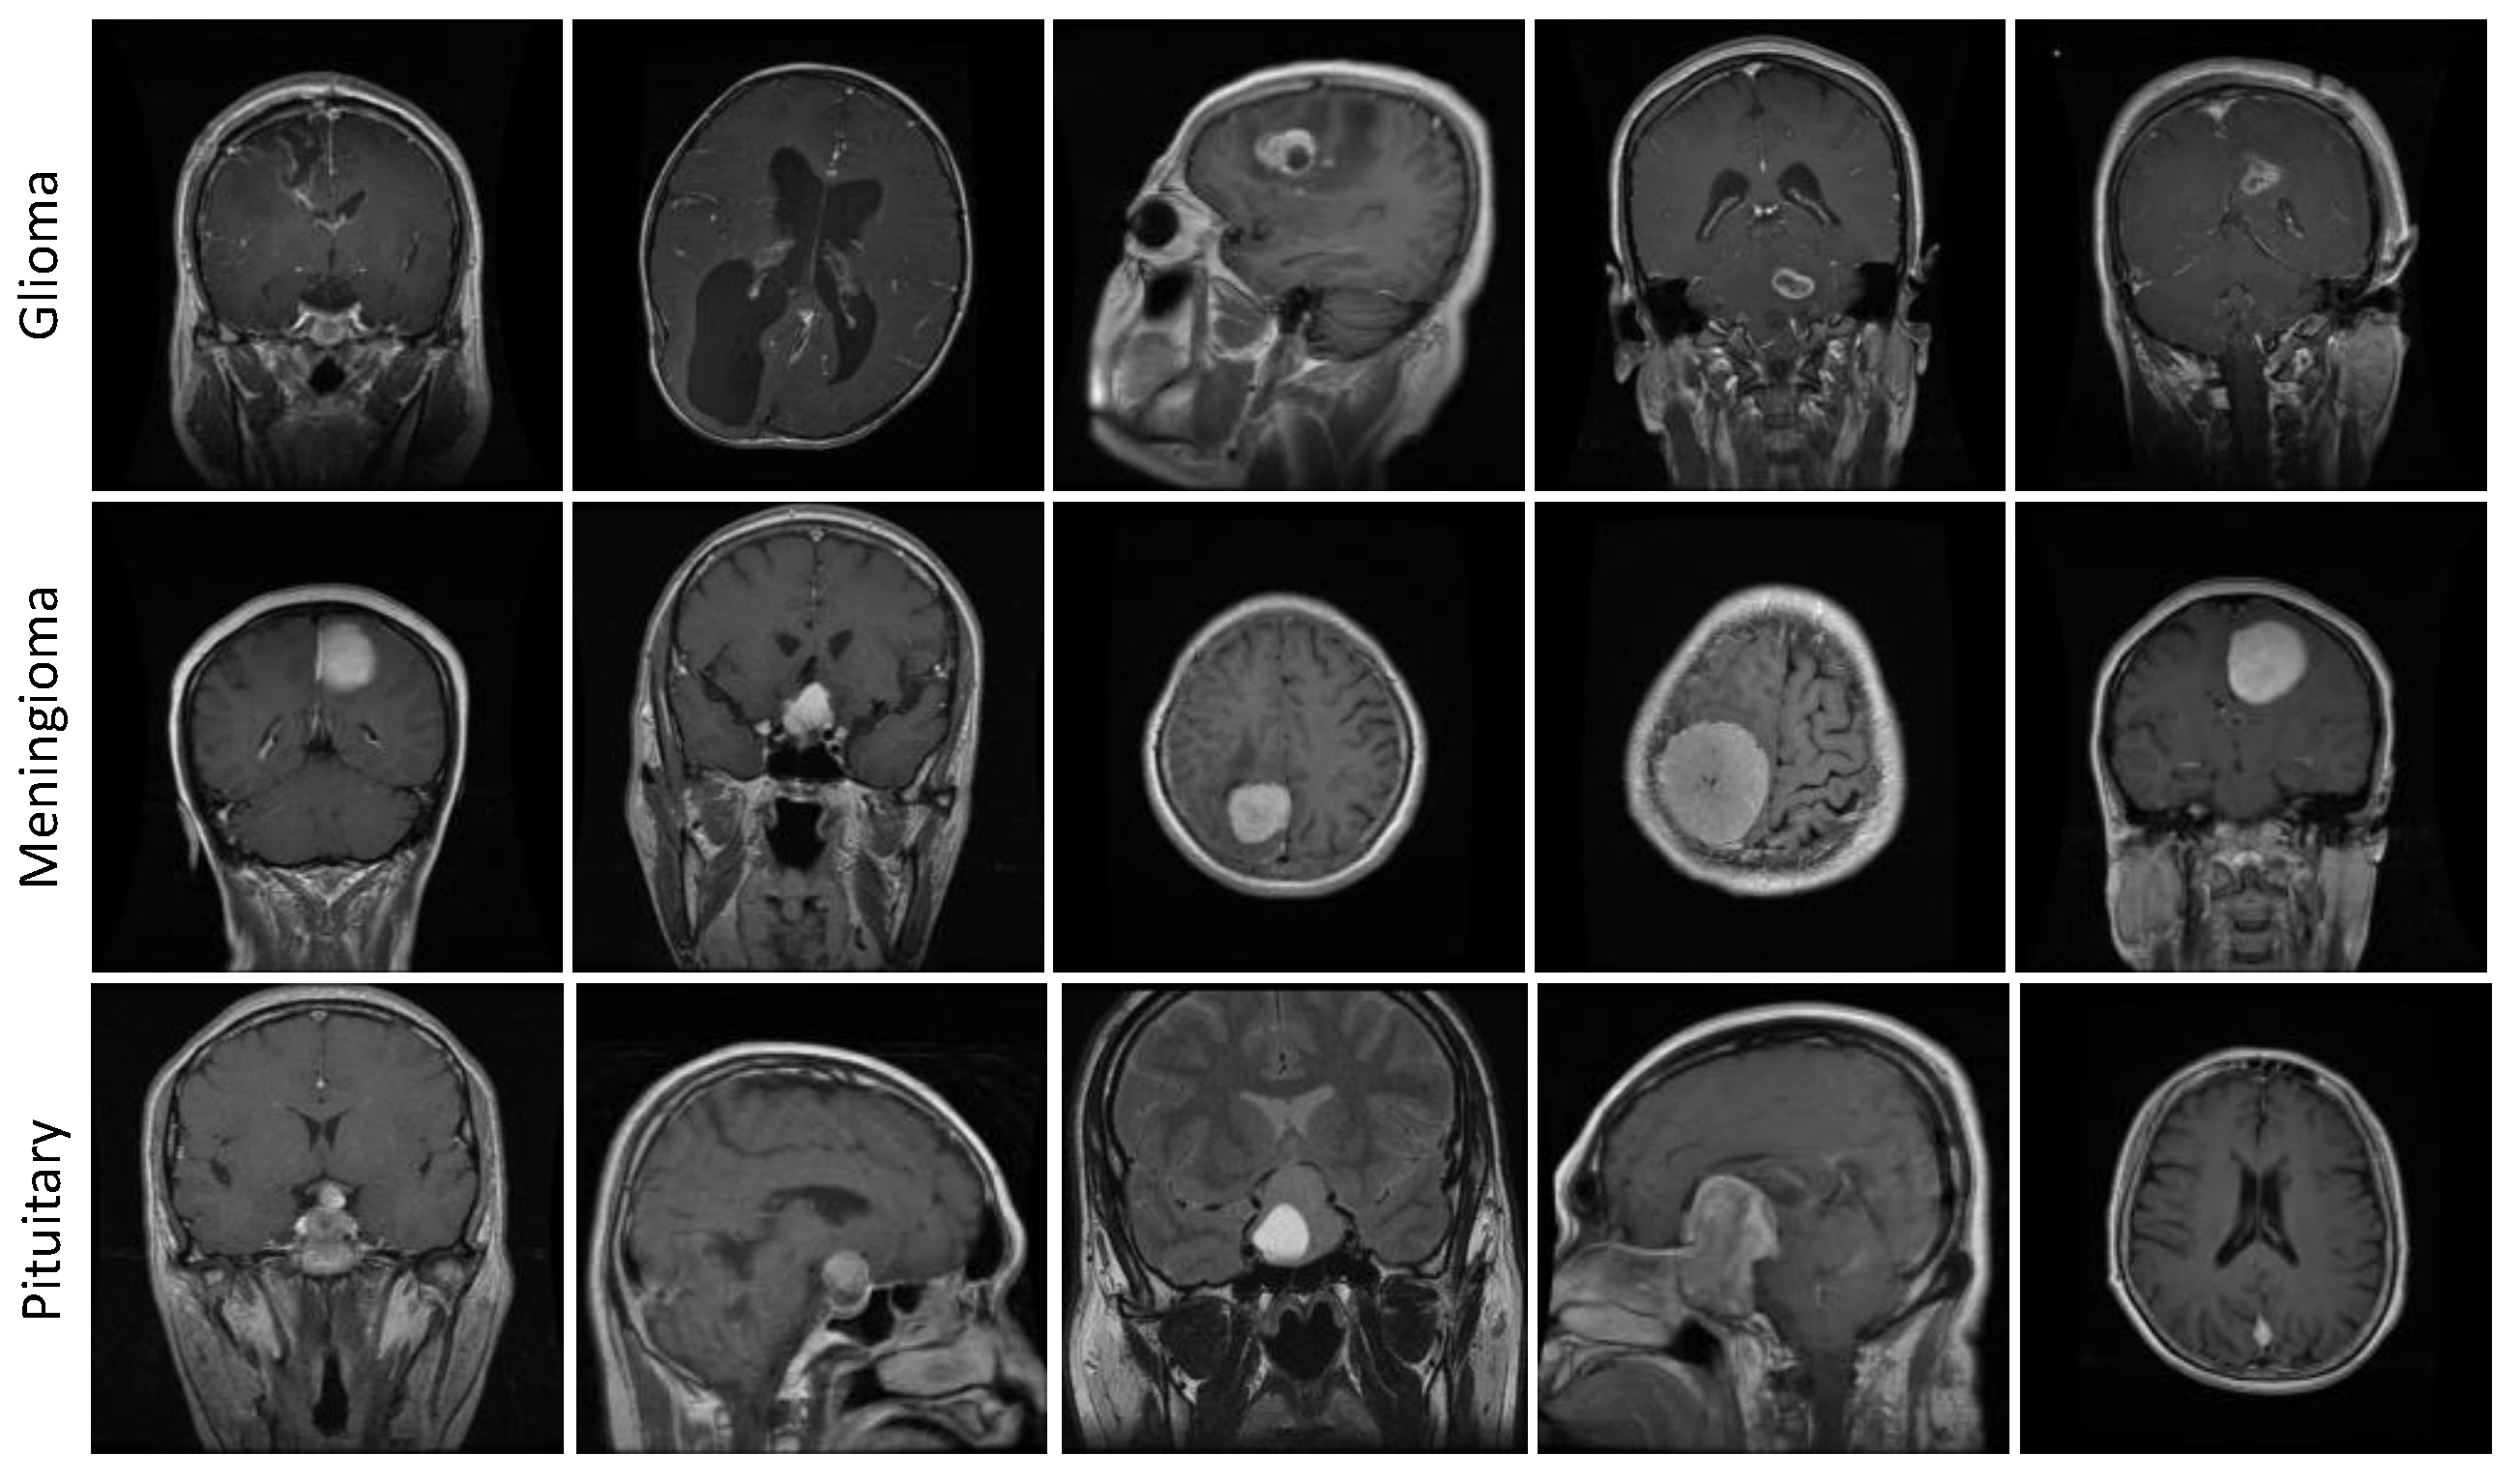

3.5.2. Figshare Dataset

4.4. Results Evaluation Using Figshare Dataset